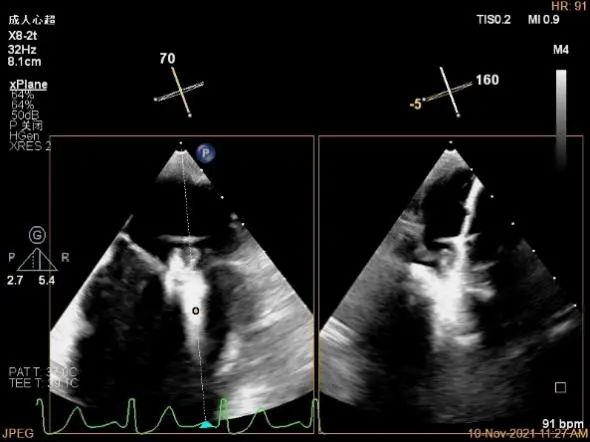

确定房间隔穿刺点:略靠前,3D视图2点位

3D测量大鞘长度2.2cm

3D视图打开夹子

3D视图下调Rotate,首先定位偏内侧2区,以固定活动度较大的瓣叶

X-plane:下夹子尝试捕获2区脱垂瓣叶

3D证实夹子外侧残余脱垂及瓣叶裂空